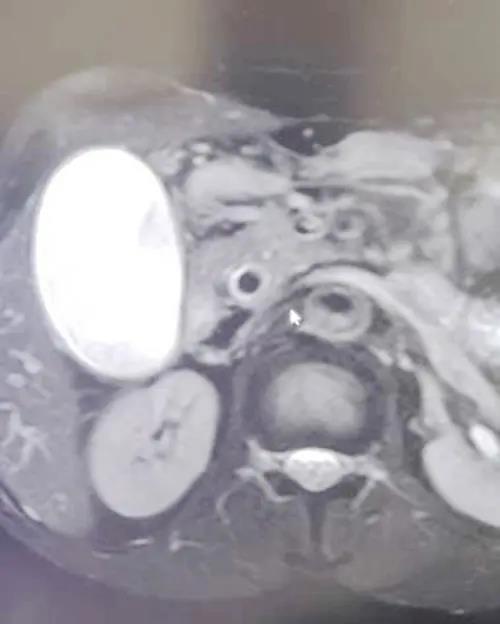

▲MRCP图片

患者女性,53岁,因“持续性上腹部疼痛不适3天”为主诉入住普外科,入院后,科室主任张永全立即召集全科医师对患者进行详细检查,并对病情进行了分析讨论,最终诊断为:胆囊结石伴急性胆囊炎、胆总管扩张。考虑到胆总管扩张原因较多,为进一步明确诊断,在得到患者及家属同意后,决定由张主任主刀,李金科副主任医师、徐亚文主治医师、崔仁杰住院医师协助在全麻下为患者行胆囊切除术+胆道镜下胆总管探查术,手术过程顺利,患者术后安返病房,目前恢复良好。

胆总管扩张原因

胆总管结石、胆管肿瘤、胰头癌、急慢性胰腺炎、胆道蛔虫、先天性胆总管囊状扩张,oddi氏括约肌狭窄、胆囊切除术后代偿性扩张、老年性生理扩张、先天因素等。